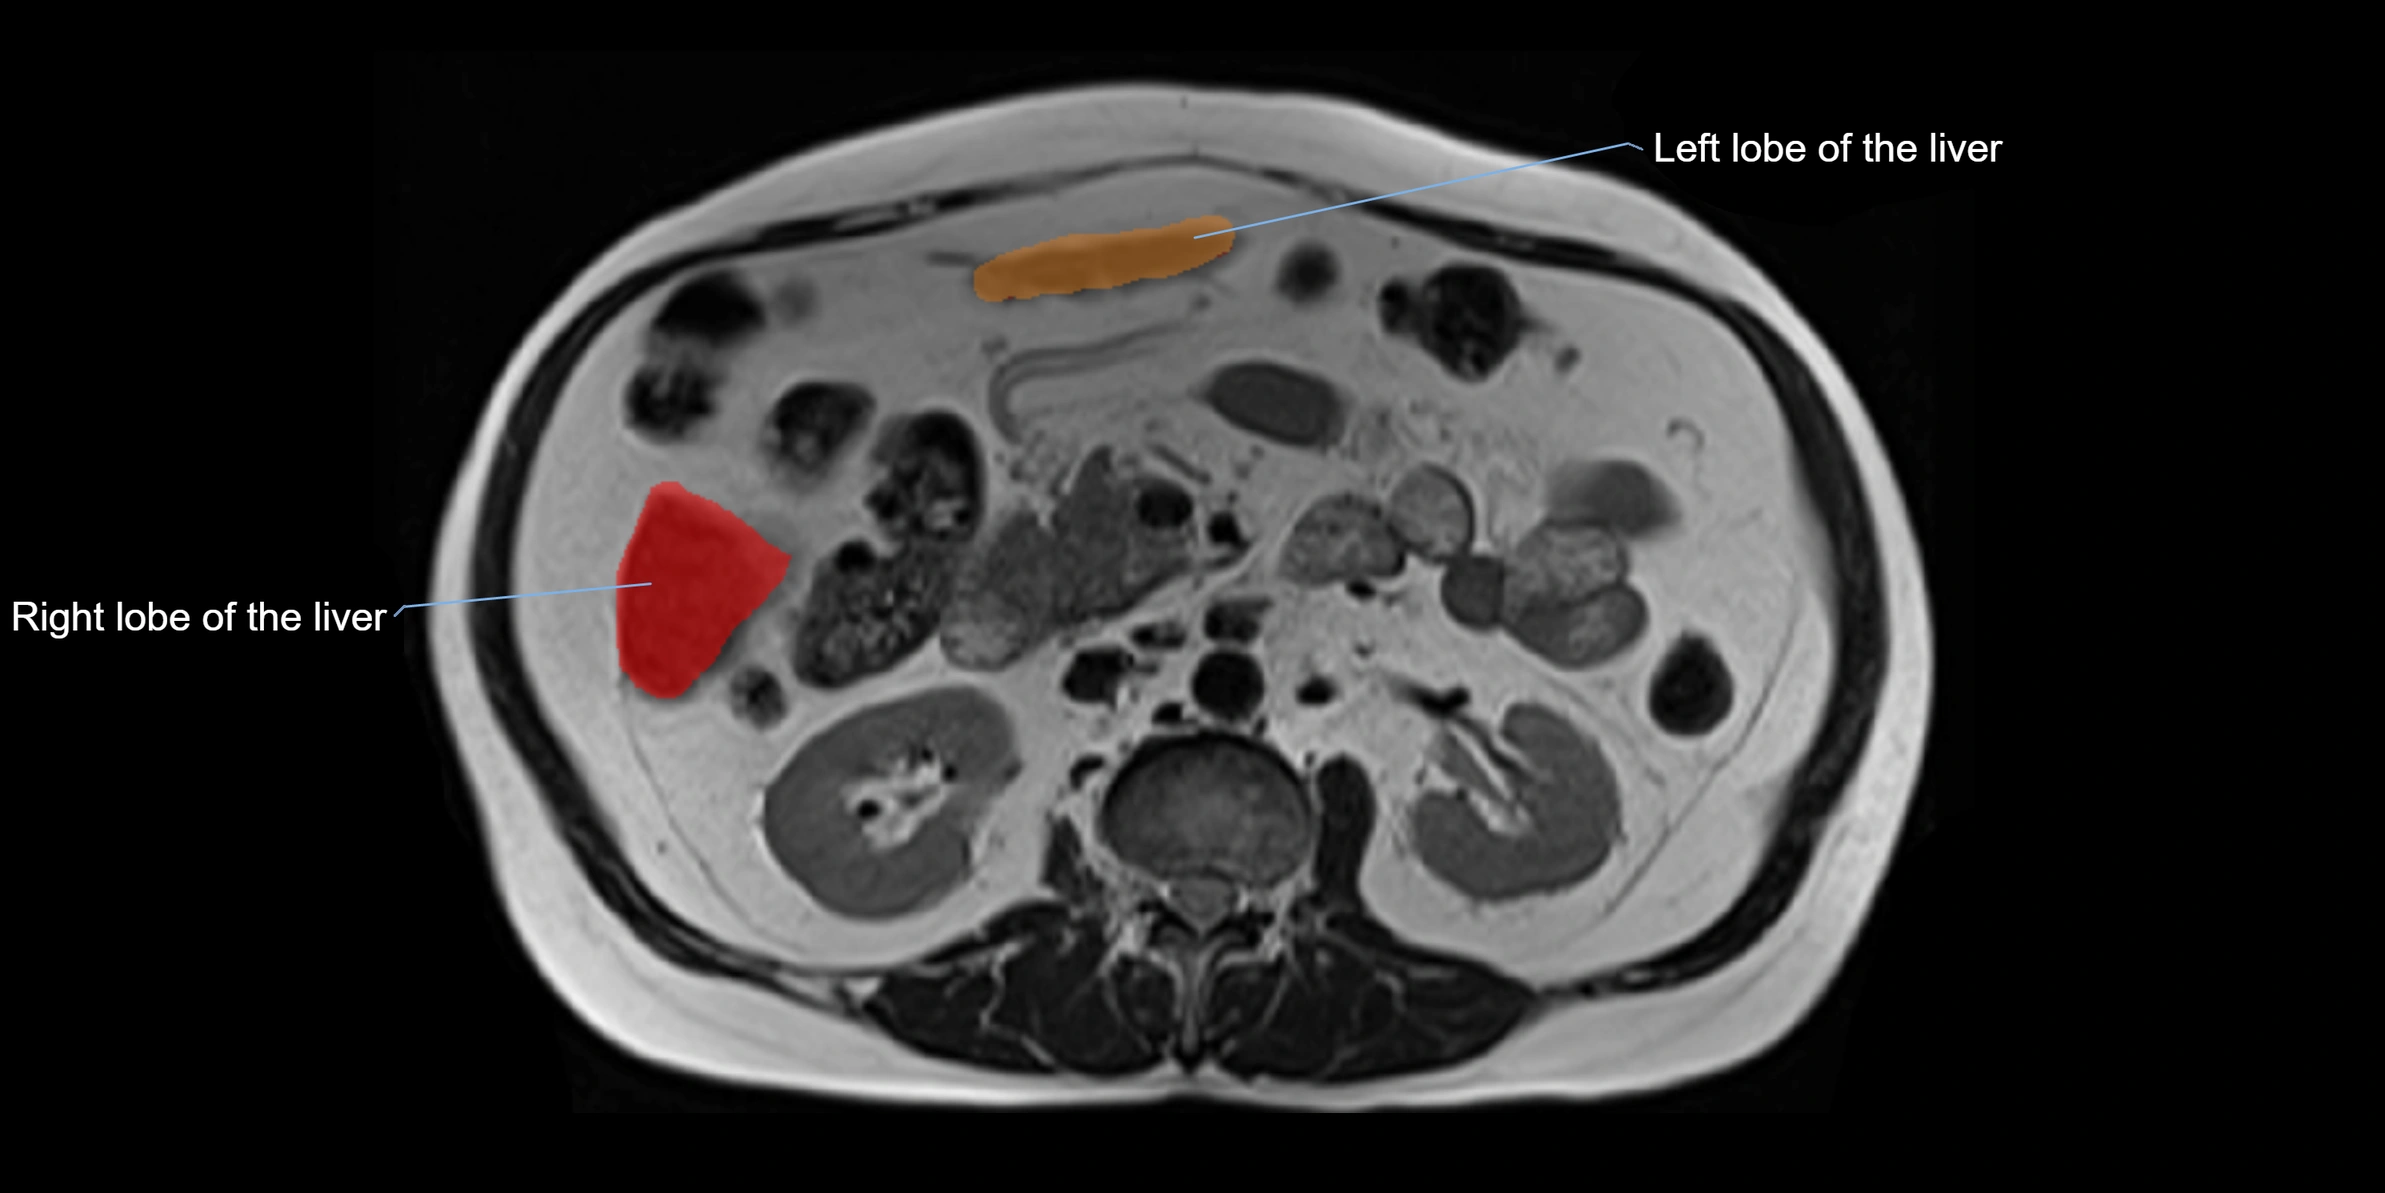

The caudate lobe of the liver is a distinct anatomical subdivision of the liver, designated as segment I in Couinaud’s classification. It lies on the posterior surface of the liver, between the fissure for the ligamentum venosum (left boundary) and the groove for the inferior vena cava (IVC) (right boundary). Superiorly, it is related to the posterior liver surface, and inferiorly it is separated from the left lobe by the porta hepatis.

This anatomical autonomy makes the caudate lobe especially significant in liver surgery, transplantation, and hepatic venous outflow obstruction syndromes (e.g., Budd–Chiari syndrome). Enlargement of the caudate lobe is a characteristic imaging feature in chronic liver disease and cirrhosis.

• Enlargement may be appreciated in cirrhosis or Budd–Chiari syndrome